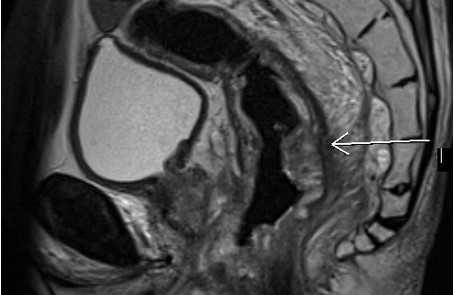

МРТ малого таза в сагиттальной плоскости. Отмечаются множественные дивертикулы сигмовидной кишки без признаков воспалительных изменений (стрелки).

МРТ малого таза в сагиттальной плоскости. Отмечается циркулярное утолщение стенок прямой кишки за счет наличия объемного образования (стрелка), распространяющегося за пределы органа в параректальную клетчатку.